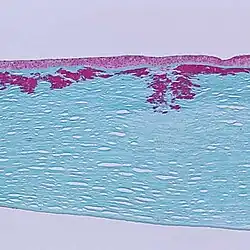

Дистрофия Рейса-Бюклерса. Отложения мутировавшей формы TGFBI в верхнем слое стромы. Из обзора Klintworth, 2009.[3]